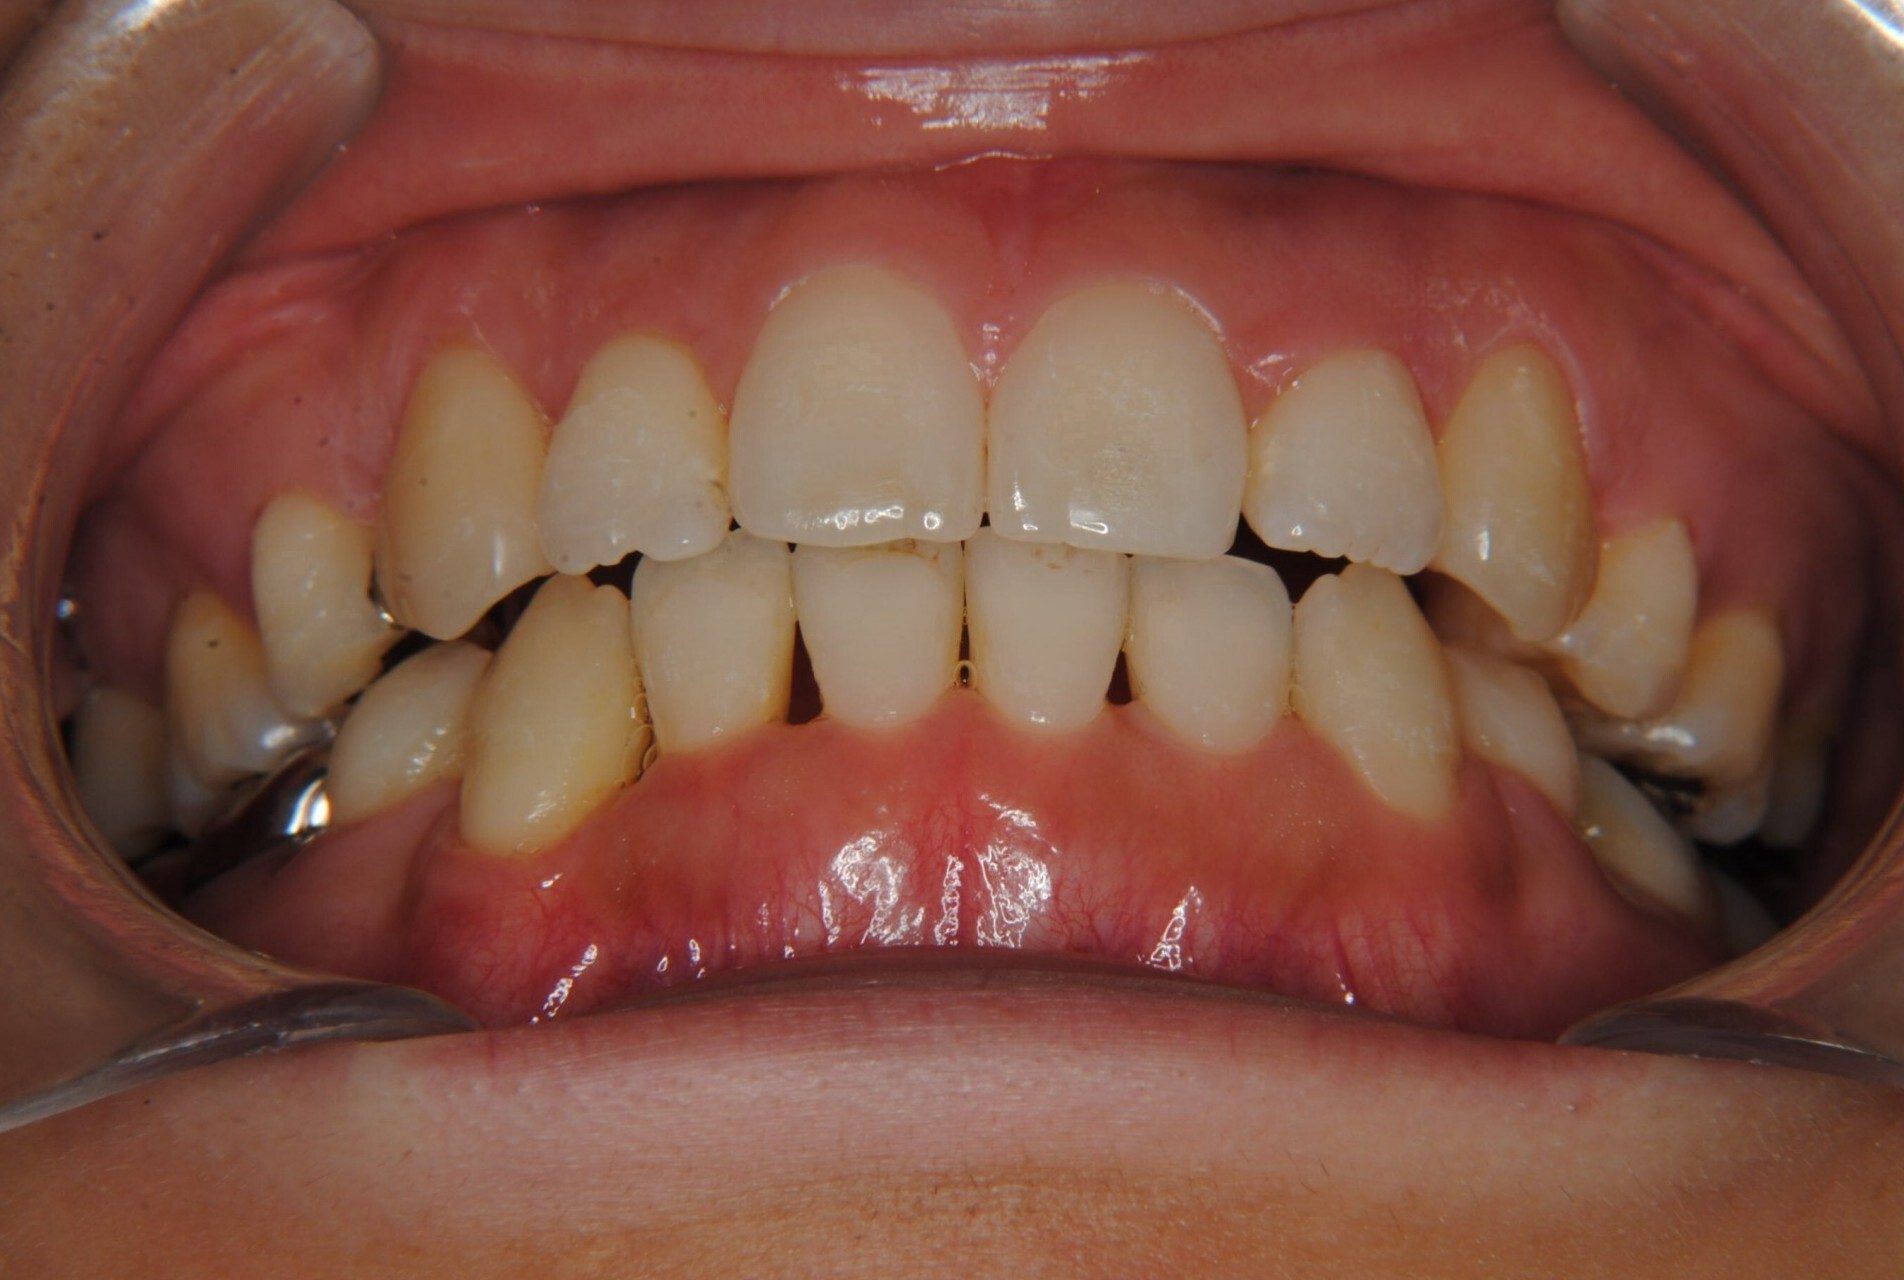

①主訴:八重歯、前歯のガタガタ、真ん中の不一致を治したい

②診断名:AngleⅠ級叢生

④治療に用いた主な装置:マルチブラケット装置(T21ブラケット)

⑤抜歯部位:上下左右第一小臼歯

⑥治療期間:1年7ヶ月

⑧リスクと副作用:マルチブラケット装置(T21ブラケット)を初めてつけてから4日間、食事の時におもに前歯が少し痛かったとのことでした。治療後のエックス線写真で、歯根吸収はほとんど観察されず、歯肉を診ると残念ながら下顎前歯部に歯肉退縮(ブラックトライアングル)が生じていました。しかし、通常下顎前歯部は下唇に隠れてむき出しにはなっていないので、ご本人はあまり気にされていないご様子でホッとしています。